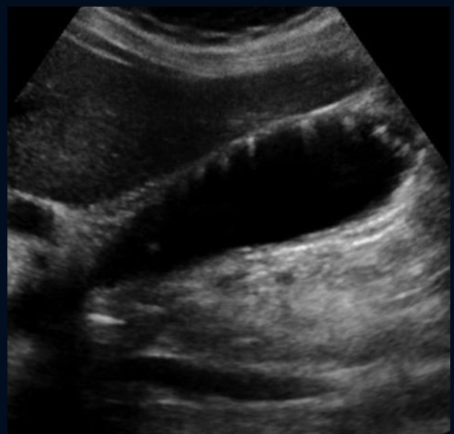

What is this?

Moderate Hydronephrosis (As it is one coherent structure there is not segmented Echogenic Structures)